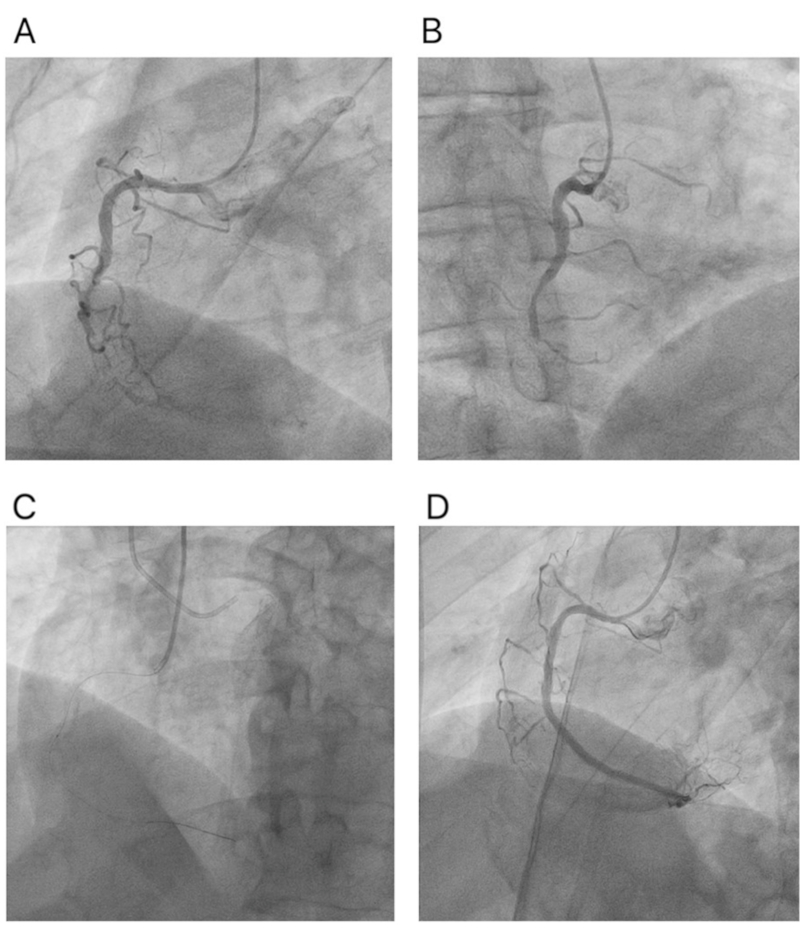

Se ingresó por la arteria radial derecha como única posibilidad de acceso vascular, mediante la técnica Bushido. Previo al procedimiento, se midió la arteria radial distal y proximal con eco-Doppler (USG) (Figuras 1 A y B). Las punciones se realizaron con la técnica de Seldinger insertando un catéter guía Ikari izquierdo (TERUMO®) 5Fr sin introductor en la arteria radial proximal y un catéter Terumo Radial TIG 5Fr en la arteria radial distal (técnica Bushido) (Figura 1 C). Se utilizó la técnica de avance asistido por balón (balloonassisted tracking [BAT]). Se realizó una coronariografía mediante doble canulación coronaria y se observó OCT (J-CTO 2 puntos) (Figuras 2 A y B). El cruce de la oclusión se logró en 20 minutos utilizando el abordaje anterógrado con escalamiento de guías. Para la predilatación, se utilizaron los siguientes balones: 1,0 × 5 mm, 1,25 × 10 mm, 1,5 × 10 mm, 2,0 × 20 mm y 2,5 ×10 mm. Debido a la presencia de una placa calcificada no dilatable, se utilizó un balón de corte de 2,5 × 10 mm; la dilatación se realizó luego con los siguientes balones: 2,5 × 15 mm y 3,0 × 20 mm. Se colocó un stent liberador de fármacos de 2,5 x 38 mm y 3,0 × 38 mm desde el segmento distal y medio de la arteria, terminando con la técnica de optimización proximal (proximal optimization technique, POT) utilizando un balón no distensible de 3,5 × 15 mm. El procedimiento finalizó sin complicaciones; la angiografía de control mostró flujo epicárdico TIMI 3, con fenómeno de no-reflow, y sin disección, perforación ni trombosis (Figuras 2 C y D). La angiografía en la arteria radial no presentó complicaciones, y la hemostasis se realizó con una banda radial distal y una proximal.